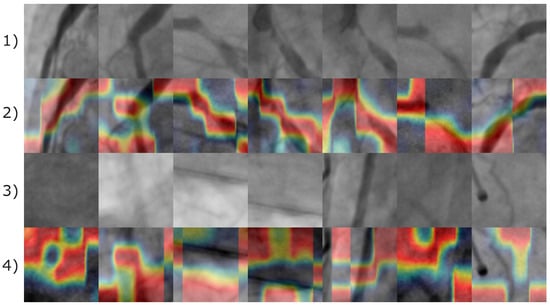

According to Figure 13, the image features leading the CNN model to produce a positive classification result are almost related to the pixels corresponding to arteries. Consequently, for negative stenosis classification results, the model involves features from arteries and non-artery pixels. In Figure 14, the corresponding Grad-CAM results from the Antczak image database are also presented.

Figure 14.

Image samples of the Antczak image database involving natural and synthetic images. The first row illustrates the original images of positive coronary stenosis cases. The second row illustrates the corresponding Grad-CAM heatmaps. The third and fourth rows illustrate the original and the corresponding Grad-CAM heatmap images for the synthetically generated instances of positive coronary stenosis cases. The fifth and sixth rows corresponds to natural images of negative coronary stenosis cases with their respective Grad-CAM heatmap. The heatmap is represented by a color gradient from red to blue denoting feature importance. Red regions highlight the most influential features, while blue denotes areas of minimal contribution to the classification.

Based on the images presented in Figure 14, the Grad-CAM shows evidence that artery pixels were also relevant to the identification of features related to positive coronary stenosis cases. Consequently, non-artery information form the image was relevant to the identification of negative coronary stenosis cases.